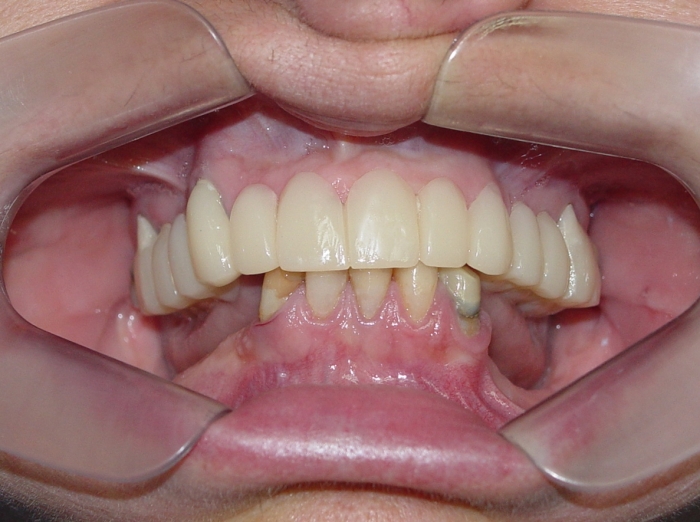

Próteses Fixas Provisórias em Setembro de 2015 - Clínica Cliniface

Próteses Fixas Provisórias em Setembro de 2015